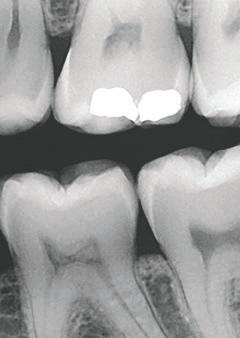

TrollBag for røntgensensorer

Supermyke trekk for sensorer og fosforplater. Helt uten lateks, lukt, smak og skarpe kanter. Lett å ta på og av, uten å ødelegge sensoren.

Tips: XL-trekket dekker både sensor og røntgenholder. En superenkel løsning som gjør hygienearbeidet mye enklere.

TrollBag for fosforplater

Supermyke poser for fosforplater.

Helt uten lateks, lukt, smak og skarpe kanter. Lett å ta på og av.

Leveres på rull i praktisk dispensereske.

Dekker sensor.

3,6*22cm.

500-pk. Før 1.048,#1

734,-

Vnr. 6509

#13190089

Dekker sensor. 4,0*22cm. 500-pk. Før 1.048,#13190090

Vnr. 6500

Fosforplate #1 49x29mm. 500-pk. Før 1.298,-

Fosforplate #2 50x36mm. 500-pk. Før 1.298,-

Vnr. 7783 974,-

Vnr. 7784

#13190401 #13190402